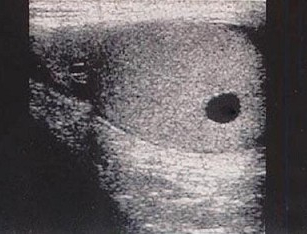

13、单项选择题

该病例最有可能诊断()

A.左房黏液瘤

B.主动脉瓣关闭不全

C.二尖瓣狭窄

D.二尖瓣关闭不全

E.二尖瓣脱垂

14、单项选择题